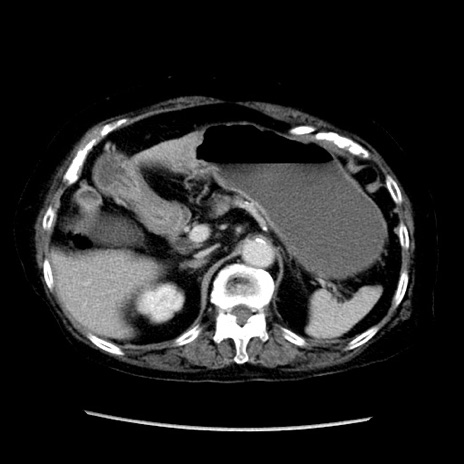

症例14(横断像)

【症例】 90歳代女性

【主訴】 腹痛・嘔吐

【現病歴】今朝から左側腹部痛を認めた。 経過観察していたが、嘔吐を認めたため来院。

【既往歴】 子宮癌術後

【身体所見】 意識清明、BP 127/54mmHg、P 98bpm Sp02 95%(RA)、BT 35.8°C、腹部平坦・軟腸ぜん動音聴取良好、右下腹部圧痛(+) 反跳痛なし

【データ】WBC 9800、CRP 0.46